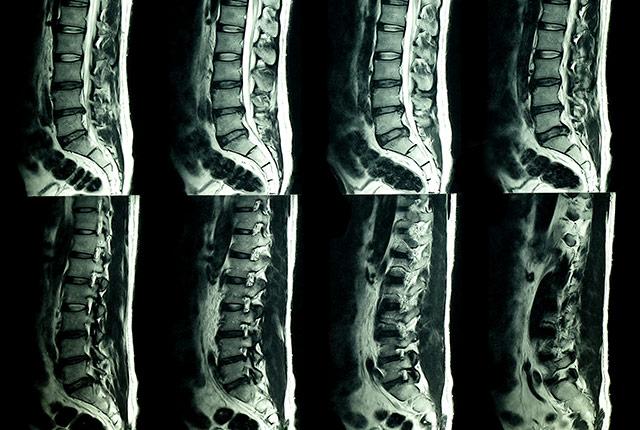

Your spine deteriorates naturally over time, even if you tread lightly and are mindful of good posture. Radiologists are keenly aware of this truth due to an endless queue of patients with low back pain whose imaging scans reveal no acute injury but, instead, show typical signs of activity, gravity, and aging.

UW Medicine researchers explored what would happen if patients’ imaging reports—terse anatomic observations of “disk height loss” and other findings—also included plain-language context that such findings are commonly seen in people who have no pain.